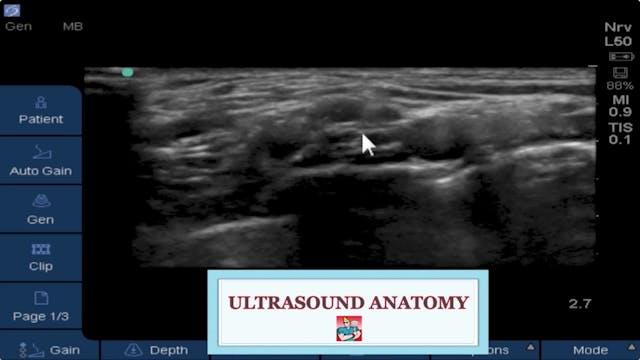

In this new Virtual Ultrasound Workshop video Dr. Brandon Winchester explains tips and tricks for the successful and safe placement of interscalene blocks and continuous interscalene catheters.

The BLOCKJOCKS Virtual Ultrasound Workshop comprehensively discusses and demonstrates scanning & technique considerations for all of the major upper and lower extremity nerve blocks and continuous catheter procedures.